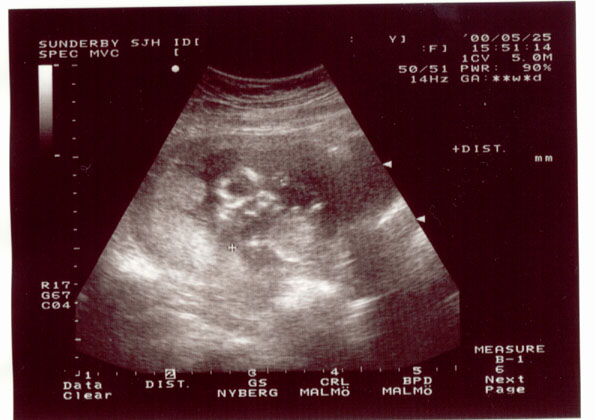

Vid det vita krysset är foten, strax till höger knäet. Ovanför syns huvudet med ansiktet nedåt, som om E.T. tittar på sina fötter.

At the white cross you can imagine the foot, next to the right the knee. Above you can see the head with the face down like E.T. watches the feet.